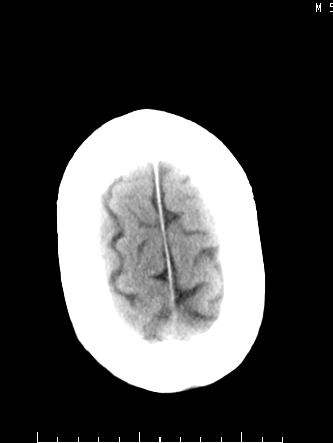

m/50,头昏头痛1月,近3天感觉左半肢体活动不利,自述半年前呈患肺tb,腰穿脑脊液未见特殊改变。现做头颅ct请大家会诊。

脑干区胶质瘤可能性大。

脑干占位,考虑转移瘤可能性大,不除外胶质瘤.

考虑为:脑干脓肿;不排除胶质瘤或转移瘤。